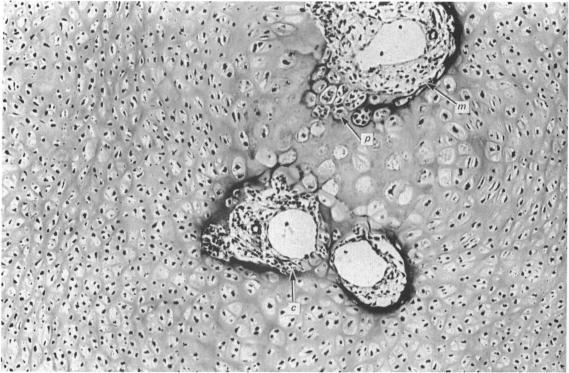

Bone formation in the vertebral centra commences within the centrum and is in this respect analogous to the secondary ossification which occurs in the epiphysis of a long bone. Bone tissue first appears at about the 85 mm C.R. stage and not in the 55 mm C.R. length embryo; at the latter stage blood vessels and calcification alone were observed. The connective tissue cells within the cartilage canal appear to assist osteogenesis by providing osteogenic cells which lay down bone in the walls of the cartilage canal, and provide cells which remove calcified cartilage found at the periphery of the canal; they assist growth by producing an appreciable number of chondrocytes that permit lateral expansion of the centra. Osteogenesis appears to occur in multiple foci within the growth plate of the older embryos and could account for the rapid rate of growth of vertebrae. Bone formation occurs in both mineralised and unmineralised matrix (as seen on the walls of the cartilage canals). The blood vessels within the growing vertebra tend to follow the zone of cartilage hypertrophy.